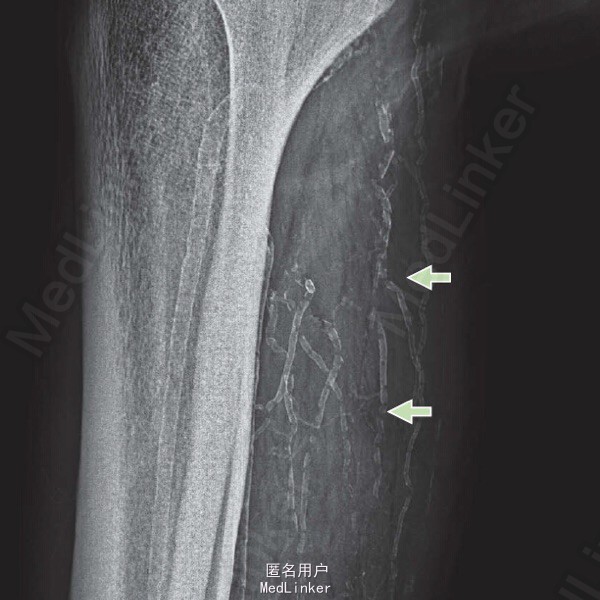

患者双侧足部脉搏可触及,未见慢性静脉功能不全。软组织 X 线检查示动脉弥漫性钙化,呈网状。 皮肤活检后组织学检查见血管硬化及血栓形成。